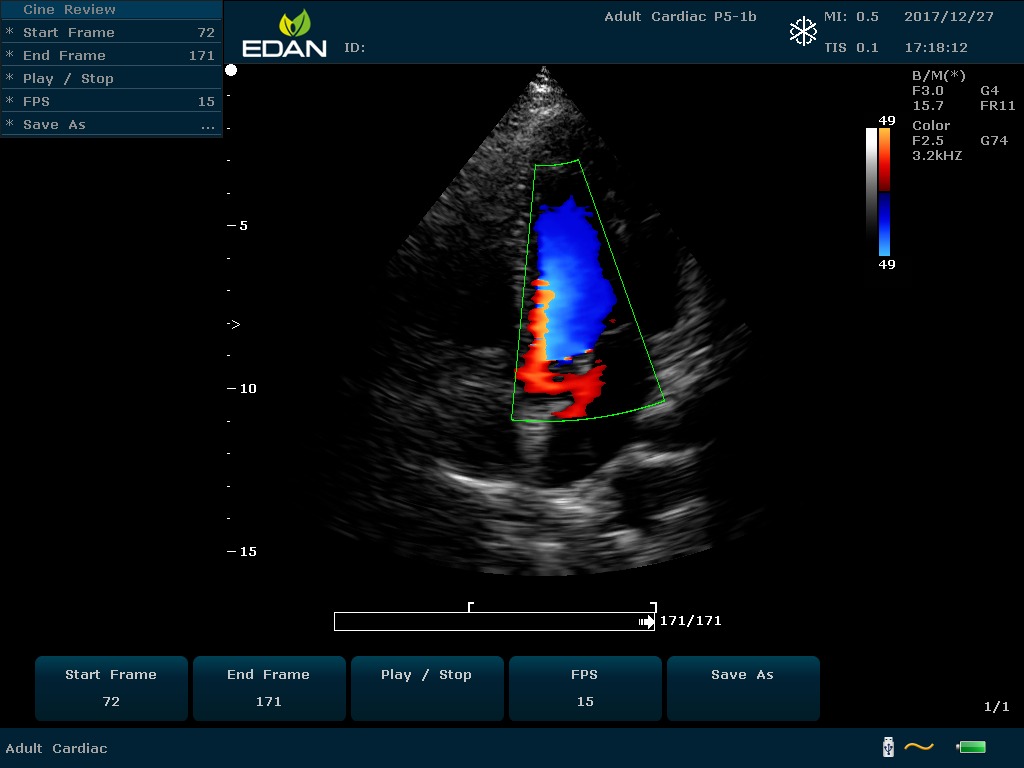

Передовые технологии позволяют повысить качество визуализации в несколько раз. УЗИ-аппарат U60 Edan отличается возможностью быстрой настройки визуализации. Специальные функции позволяют моментально отображать данные за счет быстрой оптимизации параметров. Режимы визуализации: B-mode, M-mode, Color Doppler, Power Doppler Imaging, Pulsed Wave Doppler, Continuous Doppler.

• Цветовое Допплеровское картирование

• Импульсная Допплерография

• Непрерывноволновая Допплерография

• Спектральный Допплер с высокой частотой повторения импульсов

• Направленная энергетическая Допплерография